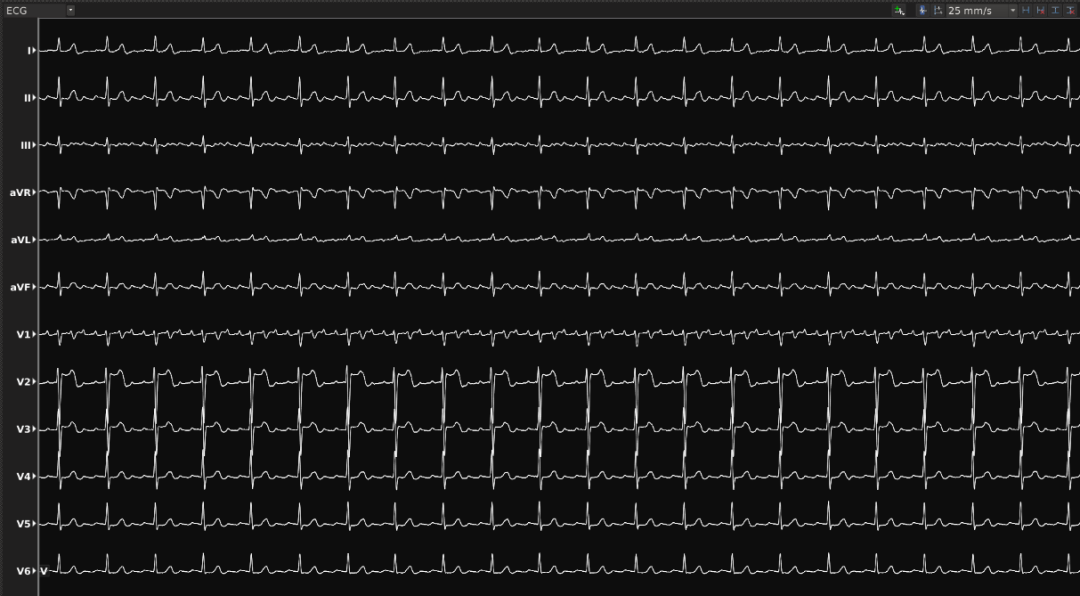

ECG

一位63岁的男性患者,二十多年前因“室上性心动过速”进行射频消融术,4年前进行肝脏移植。最近心悸持续多天不见缓解。于是该患者慕名至昆明医科大学第一附属医院就诊,后确诊为心房扑动。2022年5月25日,华宝桐主任团队对其实施房扑射频消融手术,这也是云南首例基于DIRECTSENSE™局部阻抗监测技术完成的房扑射频消融手术。

患者至手术室时心率为147次每分钟,常规消毒铺巾后,放置冠状窦十级导管,心室四极导管和Orion标测导管。在波士顿科学Rhythmia连续自动标测系统的指导下,利用Orion高密度标测导管快速标测右房。耗时7分43秒,获取有效标测点9611个(Projection Distance=2mm)。激动标测提示:冠状窦口最早激动,CL未标满,且最早点激动时间晚于CS5-6的A波,提示该房速可能来源于左房。遂穿刺房间隔至左房。利用Orion高密度标测导管快速标测左房。耗时9分钟39秒,获取有效标测点22410个(Projection Distance=2mm)。激动标测提示:左房游离壁有条阻滞线,左房后壁偏下位置有块疤痕区,房速机制绕左房后壁疤痕和右下肺静脉的逆钟向大折返。